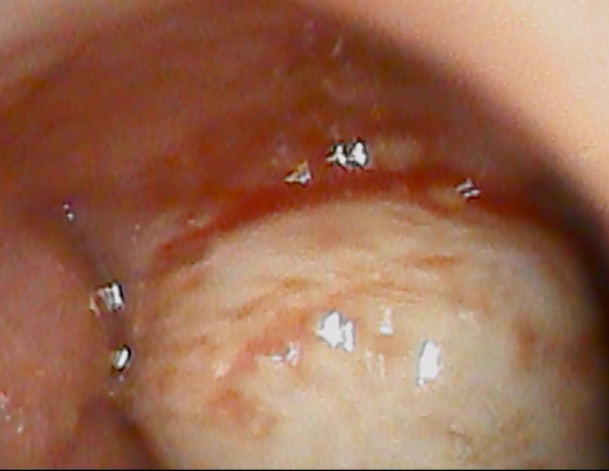

まずは右耳

鼓膜の大半は見えますが、耳垢が一番奥に入ってしまっています。

次に左耳

こちらは 耳垢で鼓膜のほとんが見えなくなっていました。

ここで耳垢について説明したいと思います。 耳垢は耳の入り口から1cmくらいの浅い場所に溜まります。奥には溜まりません。したがって 今回の場合は、何らかのきっかけで一番奥にまで入ってしまったと思われました。

お話を伺うと ご両親は綿棒で定期的に掃除していたとのこと。

今回は 吸引機でなんとか耳垢を除去することが出来ましたが、軟らかくする点耳薬処方し次回除去という子供さんも多いです。

耳掃除はほどほどがベストです。皆さん気をつけましょう